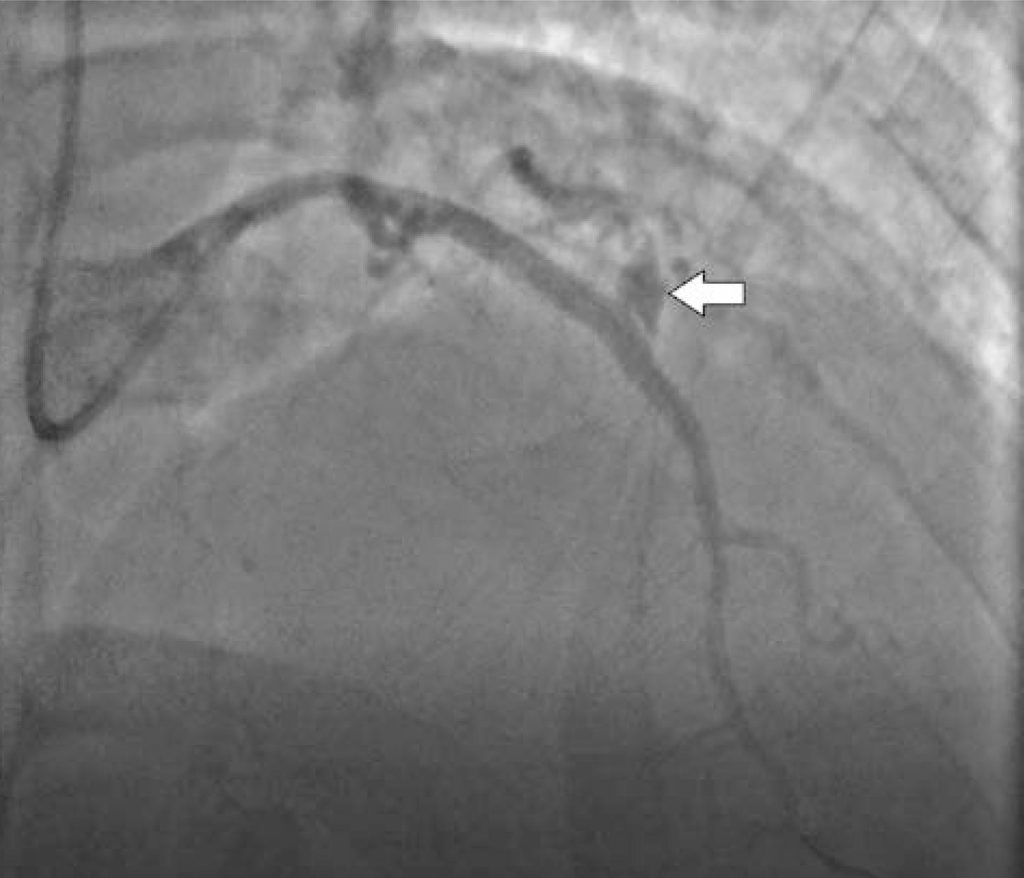

Figura 2

Perfuração em descendente anterior tipo III intra-stent (seta branca), com franco extravasamento para o pericárdio.